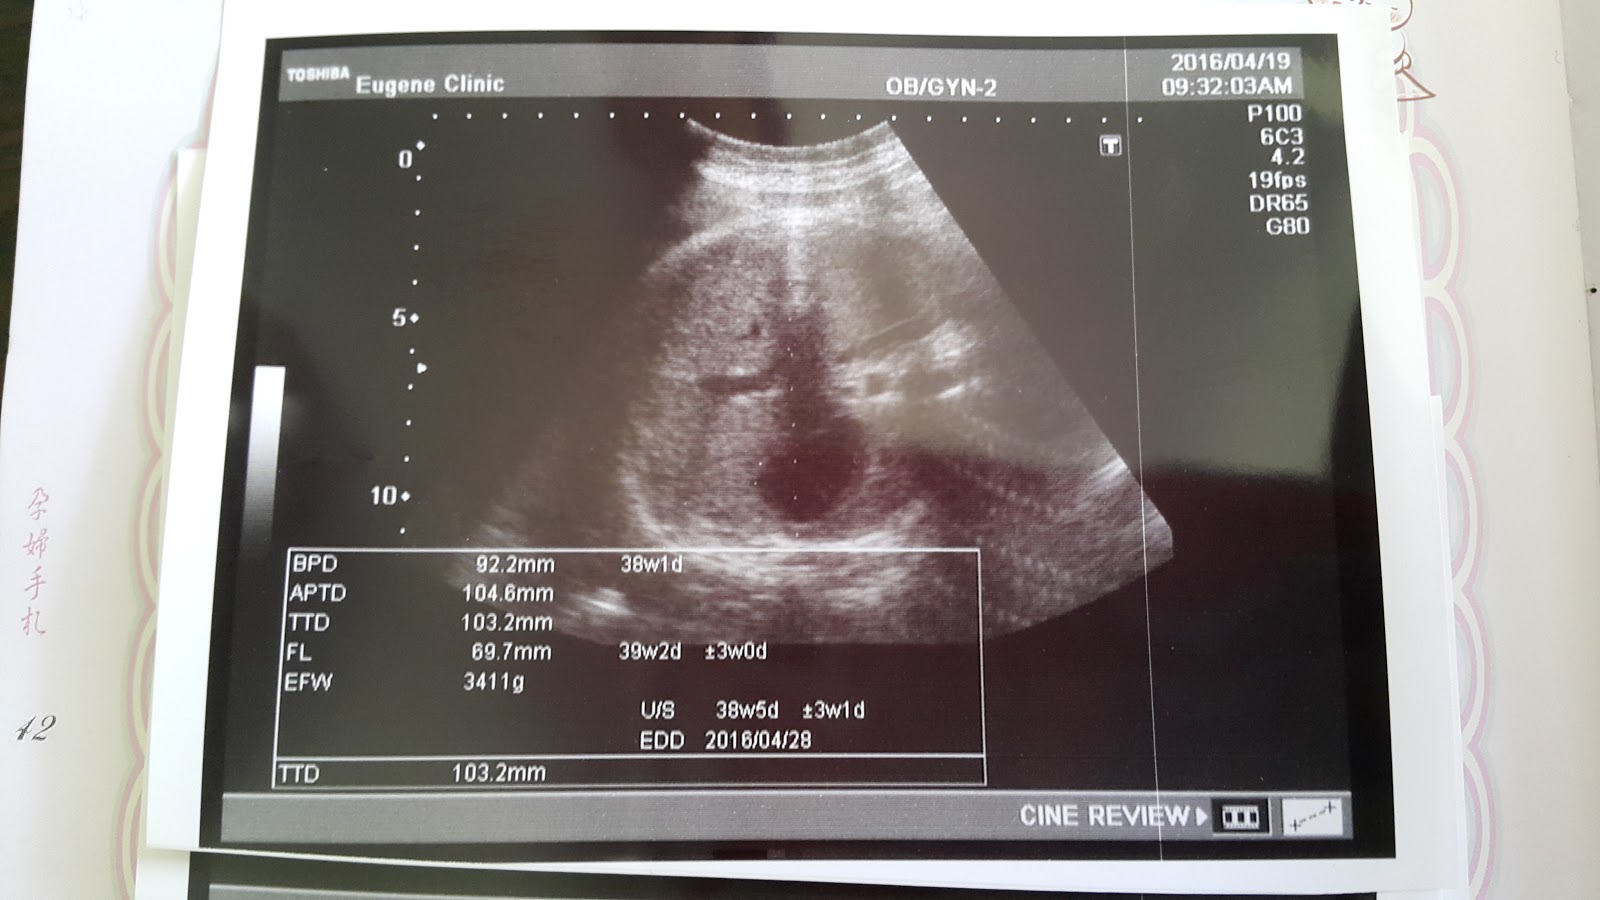

醫生做完超音波,看完妳的體重,問了哥哥當時出生多重

你現在已經3400g了,差了700g有

醫生說明天晚上來辦住院吧!體重差的有點多,怕媽媽太難生